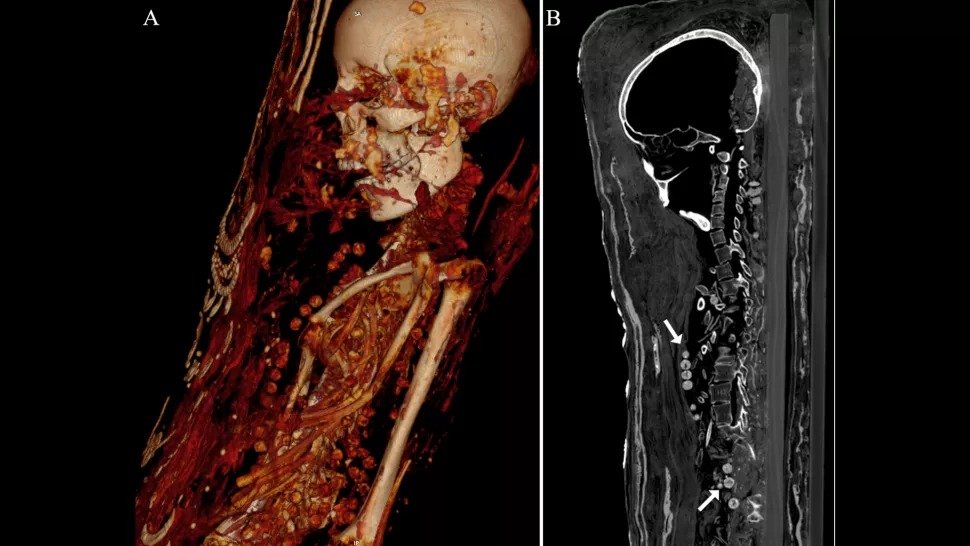

CT (computed tomography) scans show that one of the three plaster-coated mummies was buried with organs (even brains), and two women were buried with beautiful necklaces, the researchers found.

A CT scan shows the beads of a necklace on a woman's neck and body. (Zesh et al., PLOS One, 2020).

Computed tomography showed that mummified people – a man, a woman and a teenage girl lived in the late Roman period (30 BC – 395 AD).

The mummies were buried with artifacts believed to be useful in the afterlife, including coins, possibly intended to pay for Charon, a Roman and Greek deity who transported souls across the Styx River.

The CT scan also revealed several health problems, including the woman's arthritis.

Computed tomography showed that the man died between the ages of 25 and 30. His height was about 163 centimeters, he had two unerupted molars and several cracks in the bones.

Although the man's brain has not survived, there is no evidence that it was removed. Also, many of the embalming substances were not used. Instead, it was wrapped and painted.

According to Xesh, the two metal objects found during the investigation are most likely seals from the mummification workshop that processed his remains.

The woman, who died between the ages of 30 and 40, was about 151 cm tall. She had advanced arthritis in the left knee. The teenager, according to computed tomography, died between the ages of 17 and 19 and was about 156 cm tall.

According to the researchers, she had a benign tumor in her spine known as vertebral hemangioma, which is more common in people over 40.

Both women are buried with many necklaces.